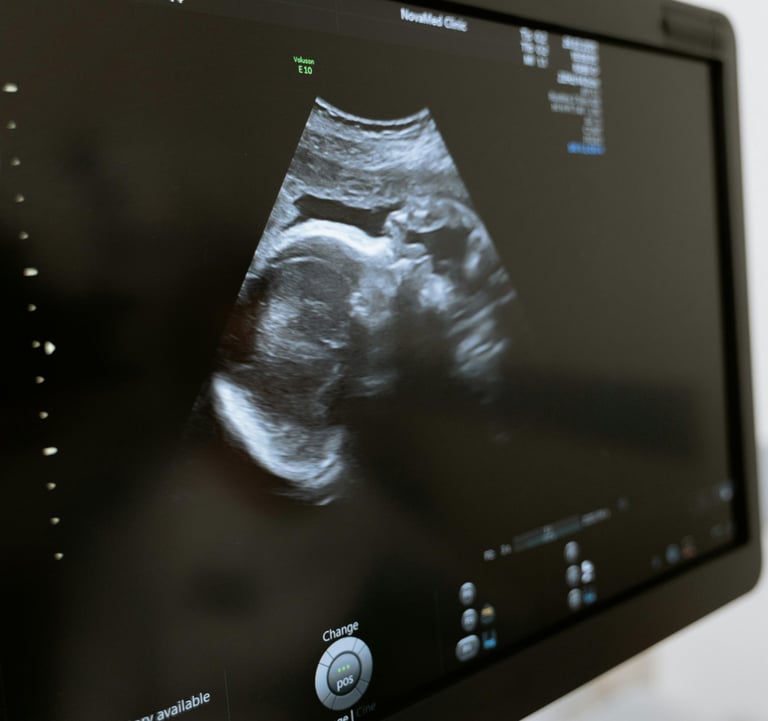

RADIOLOGÍA

Embárquese en este viaje educativo y conquiste el futuro de la radiología, donde el conocimiento avanzado se combina con la práctica , preparándolo para sobresalir en una carrera llena de oportunidades y logros.

El área de radiología, con docentes altamente calificados para brindarte lo mejor en esta nueva era de la inteligencia artificial y cómo cambia todo lo que sabemos del área, además de tener contenido de radiología, también habrá informática. x contenido de radiología para mantenernos actualizados en todo lo relacionado con PACS, HIS, LIS, RIS.

Además, contaremos con simuladores de diversas modalidades para ayudarte y una biblioteca exclusiva para que los estudiantes accedan cuando quieran.